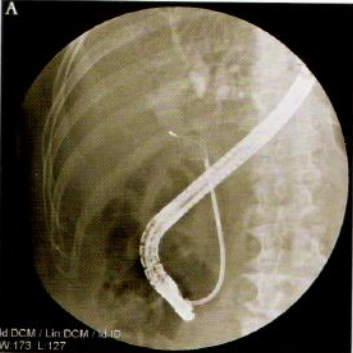

通过经内镜乳头切开(EST)技术可以使80%的胆管结石顺利取出,小于1cm的结石,一般均可通过网篮、球囊完整取出。但对于较大结石,特别是大于2cm的结石直接用网篮或球囊取出会比较困难,强行取出可能造成乳头撕裂、穿孔或结石嵌顿因此,对于大于2cm的结石,应在EST后进行碎石,再用网篮或球囊取石(图10-6-1)。

图10-6-1 | A、B.  胆管内碎石器碎石;C. 碎石后取出乳头